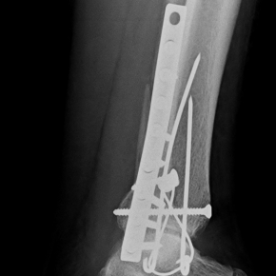

Röntgenbilder